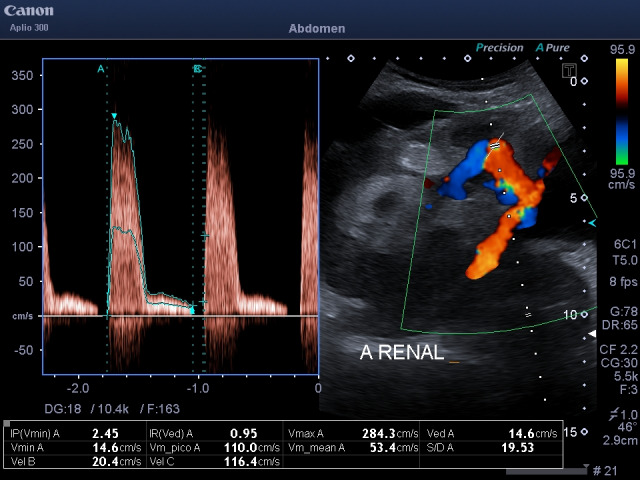

Abstract Image